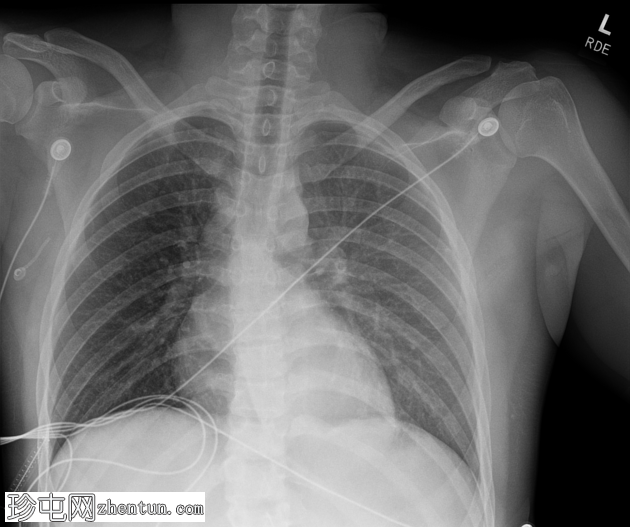

X线片

左侧胸腔弥漫性模糊影,可能为后方分层血胸,其他方面正常。

左侧后方分层血胸。